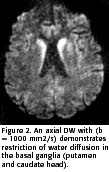

Recently, many authors reported cases of sCJD with typical findings at magnetic resonance imaging (MRI) in 67 to 79% of cases. The patients studied showed classic hyperintensity of the cerebral cortex and basal ganglia (putamen and caudate head) on T2-weighted images (T2W), FLAIR and diffusion-weighted (DWI) sequences, in both the early and late stages (more than 4 months after the onset of symptoms). This finding is indicative of restricted water diffusion and is seen mainly in the basal ganglia. The T1-weighted sequences are usually normal but may demonstrate slight hypointensity in the basal ganglia. The contrast enhancement does not occur (2, 4-10). According to these authors, these typical imaging findings, mainly the DWI findings, in conjunction with the classical clinical presentation, could facilitate the antemortem diagnosis of this rare entity.

The MRI was performed 3 months after the onset of symptoms and demonstrated marked hyperintensity in the basal ganglia on T2W, FLAIR and DWI sequences (Figure 1 and 2). Hyperintensity in the basal frontal cortex was also noted. The T1W images showed a faint hypointensity of the basal ganglia and no contrast enhancement. The apparent coefficient diffusion (ADC) in the striatum was 0,52 x 10-3 mm2/s (mean 0,74 ± 0,12 x 10-3 mm2/s in voluntary subjects, 64,9 ± 14,2 years) (5).